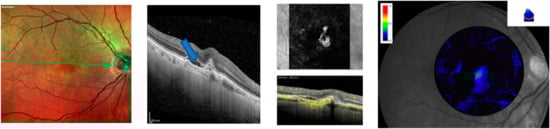

Figure 1. Multicolor imaging, spectral optical coherence tomography (SD-OCT), OCT angiography (OCTA), and macular pigment (MPOD) of active macular neovascularization in the right eye of a male 70-year-old patient before intravitreal injections of faricimab. The blue arrow shows intraretinal fluid and upper reflective material at the level of the external limiting membrane (ELM) and ellipsoid zone (EZ). OCTA reveals a dense vascular network in the macular region. MPOD shows a marked reduction in MPOD volume (blue color).

A notable improvement in the integrity of the external limiting membrane (ELM) was observed in all of the study participants. SD-OCT imaging revealed a discernible reconstitution of the ELM architecture, characterized by a more distinct and continuous hyper-reflective band in the outer retinal layers (Figure 1 and Figure 2). This phenomenon was observed across loading dose follow-up time points, suggesting a positive and sustained response to faricimab. Concomitant with the improvement in ELM integrity, our results also demonstrated a significant restoration of the ellipsoid zone (EZ) in the treated eyes (Figure 2). The EZ, corresponding to the junction between the inner and outer photoreceptor segments, exhibited a more well-defined and continuous reflectivity pattern on SD-OCT scans post-treatment. This finding was particularly evident in regions previously affected by pathology, indicating a positive impact of intravitreal injections of faricimab therapy on the structural integrity of the photoreceptor layer (Figure 1 and Figure 2).